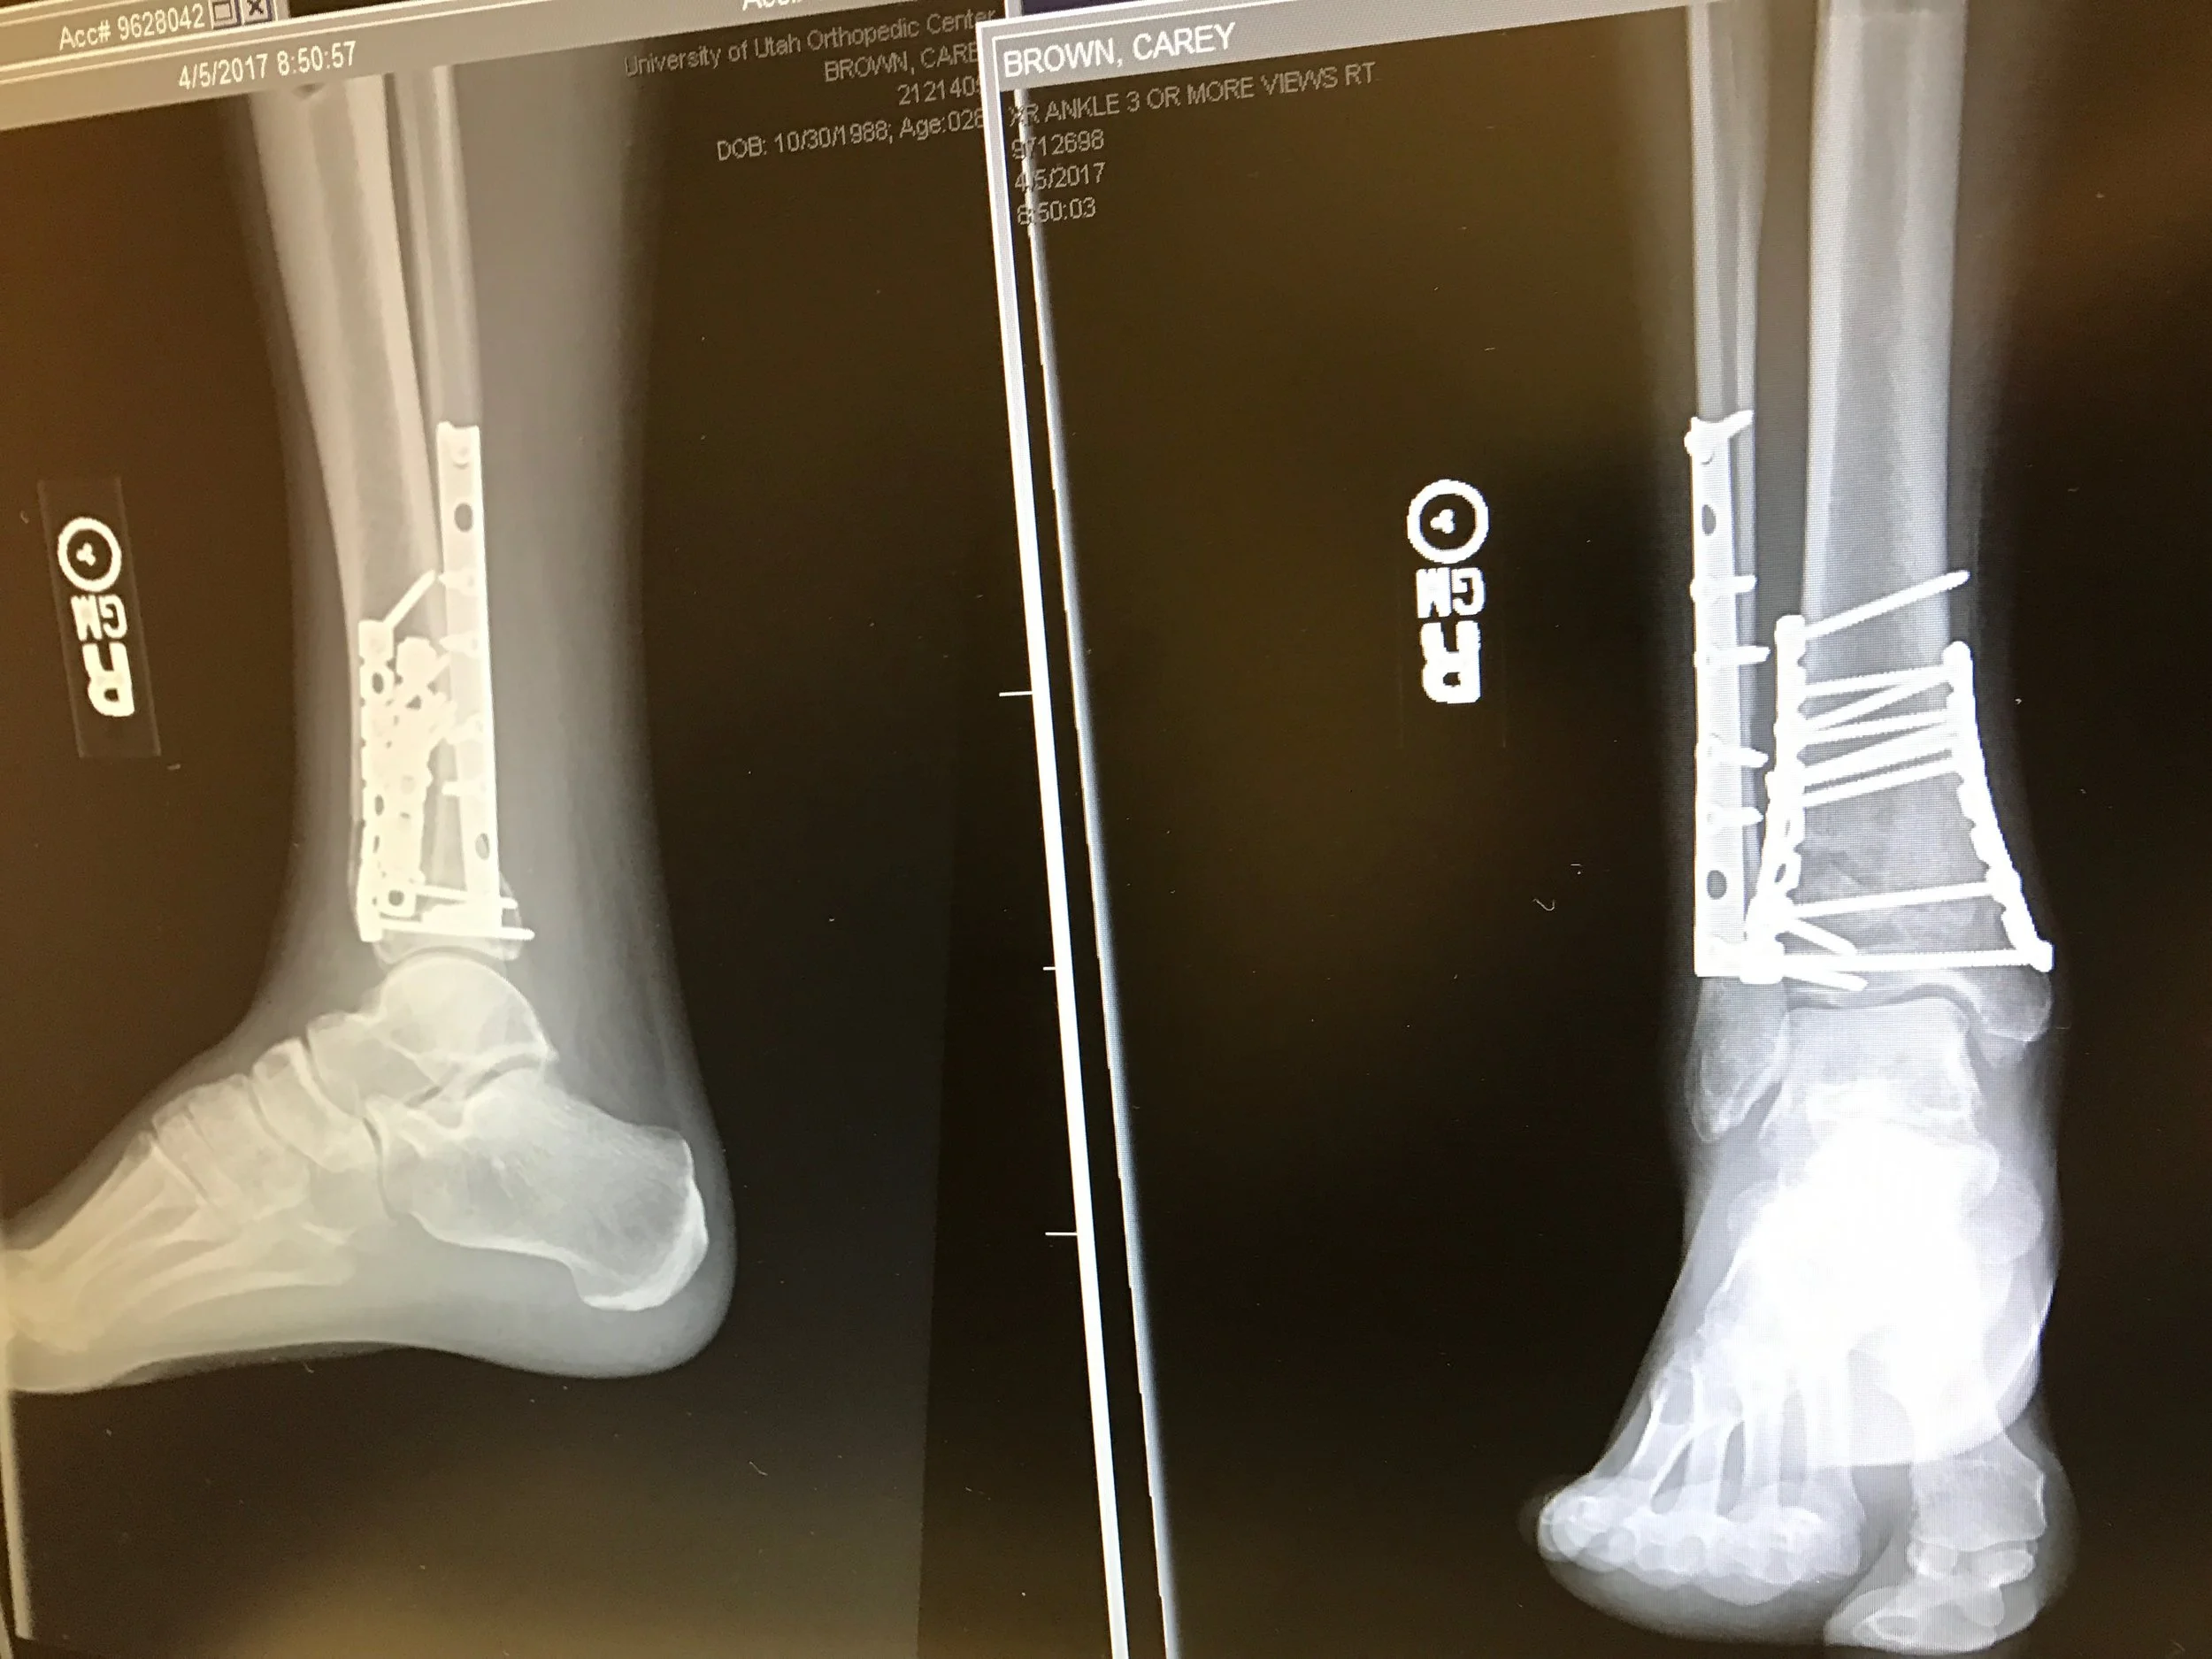

I shattered my leg. After assessing my back wasn’t broken and I could feel my toes, I sat up and knew immediately my leg was broken. Looking down at my unusable dexterity, I said to myself “I shouldn’t have been here.”

It’s now May. I’m walking again, though barely. After three months of no weight bearing, my right leg is ready to move again, but not my foot, and I have to deal with significant nerve pain in my heel. I may be able to start walking again, yet I was specifically told no running and no flying. Two things that bring me peace. My leg isn’t ready.

I guess I was able to write this down. I’ll never be able to fully articulate this part of my life. In years to come, it will look like a blip in my life story. Though, I have three frankenstein scars on my leg as a forever reminder. And how grateful I am for these scars. They will always remind me of where I’ve been, where I am, and where I will be going.